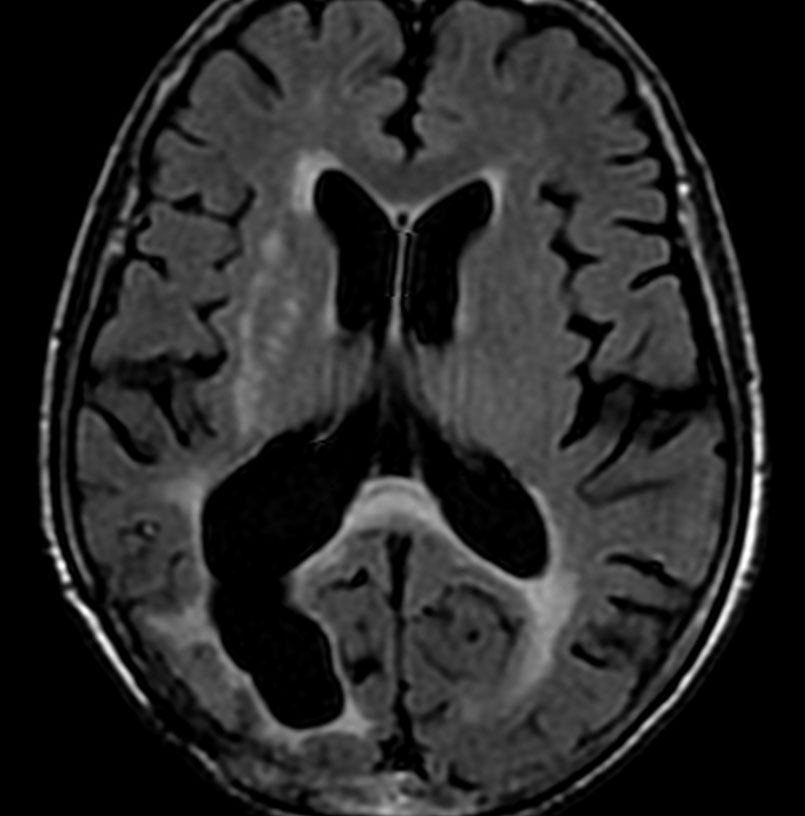

70歳女性の右後頭葉退形成性星細胞腫に対して,摘出術と54グレイ27分割の局所放射線治療をしました。右後頭葉に腫瘍摘出腔があって腫瘍再発はないのですが,治療一年後くらいから脳梁の脳室側にFLAIRで高信号の領域が広がってきました。特に星細胞系腫瘍の場合に,局所浸潤再発とまがうような所見となることもあります。ここにあげた例は典型的なもので,脳梁膨大部から膝部に至るまで脳梁内側部の白質変性が明瞭にとらえられます。